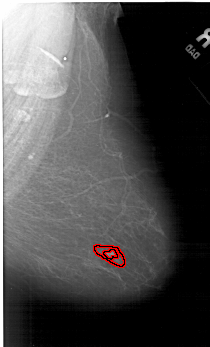

FILE: A_1255_1.RIGHT_MLO.OVERLAY

TOTAL_ABNORMALITIES 1

ABNORMALITY 1

LESION_TYPE MASS SHAPE IRREGULAR MARGINS ILL_DEFINED

ASSESSMENT 5

SUBTLETY 4

PATHOLOGY MALIGNANT

TOTAL_OUTLINES 2

BOUNDARY

CORE